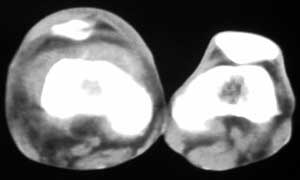

标题: CT4055:骨肉瘤?

男56涨疼5-6月

右股骨下端包绕股骨见巨大软组织肿块,密度部俊,周围见瘤骨,下端骨皮质侵蚀变薄,骨质周围无骨膜反应, 考虑右股骨软骨肉瘤。

右股骨下段周围软组织肿块伴钙化,相邻股骨骨皮质受累,考虑软组织来源恶性病变

右股骨下段骨肉瘤,软组织内瘤骨,软组织肿块。